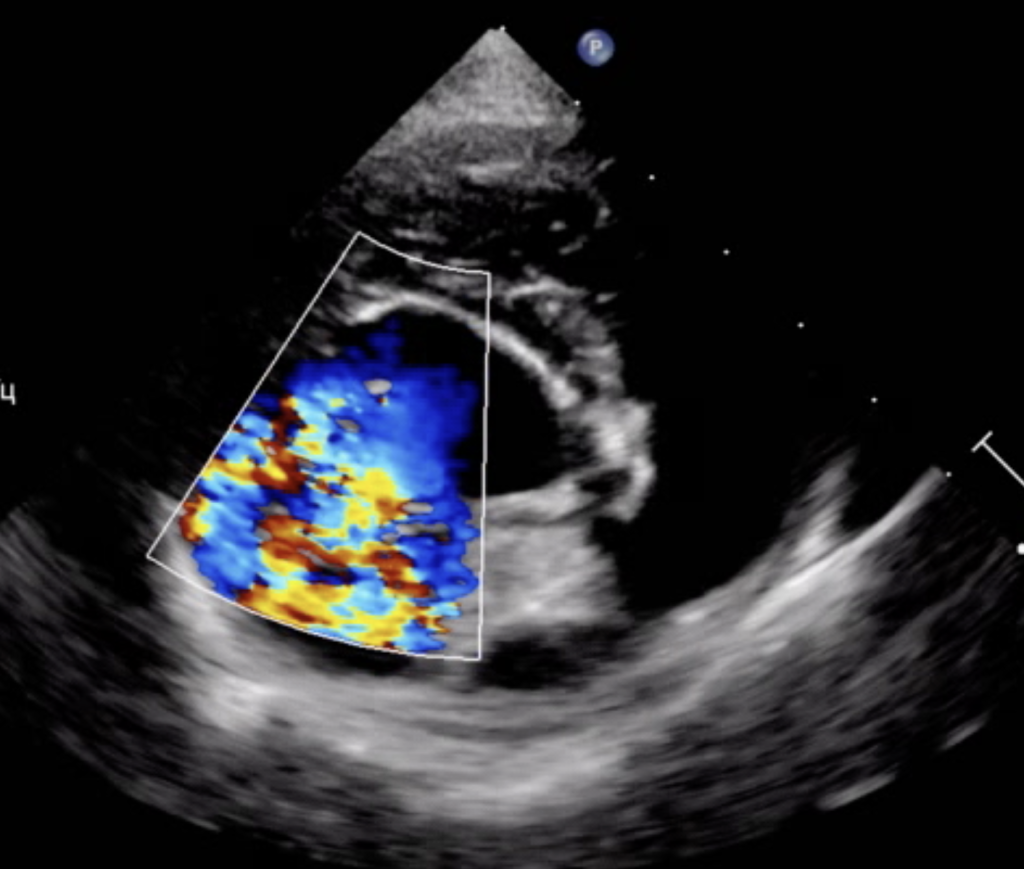

Эхокардиографическое исследование выявило пролапс передней створки митрального клапана в сегменте А2, обусловленный отрывом хорд первого порядка (фото 1, 2). Этот дефект приводил к тяжелой митральной регургитации, что проявлялось одышкой, кашлем, снижением физической активности пациента.В связи с этим было принято решение о проведении хирургического лечения, включающего аннулопластику митрального клапана и коррекцию пролапса створки по методу Альфиери.

Фото 5-7. Двухмерная эхокардиография, правая парастернальная проекция, короткая ось, срез на уровне створок митрального клапана: значительное улучшение коаптации створок митрального клапана, регургитационные потоки формируются по краям от зоны их стягивания (фото 5); створки клапана стянуты край-в-край в сегменте А2, что обеспечивает основную пропускную способность клапана через зоны А1–Р1 и А3–Р3 (фото 6). Выраженное обратное ремоделирование миокарда левого желудочка (фото 7): уменьшение конечно-диастолического нормализованного размера ЛЖ до 1,3 (до операции КДРн – 1,9).

Пациент успешно стабилизировался в послеоперационном периоде.В течение первых дней наблюдалась умеренная апатия, однако аппетит был сохранен, что является положительным признаком восстановления. Эхокардиография, проведенная после операции, выявила значительное снижение степени митральной регургитации и уменьшение давления в левом предсердии с 19/13 мм рт. ст. до 11/4 мм рт. ст., что свидетельствует об успешной коррекции дефекта клапана и об эффективности проведенного хирургического вмешательства2 (фото 5-7).